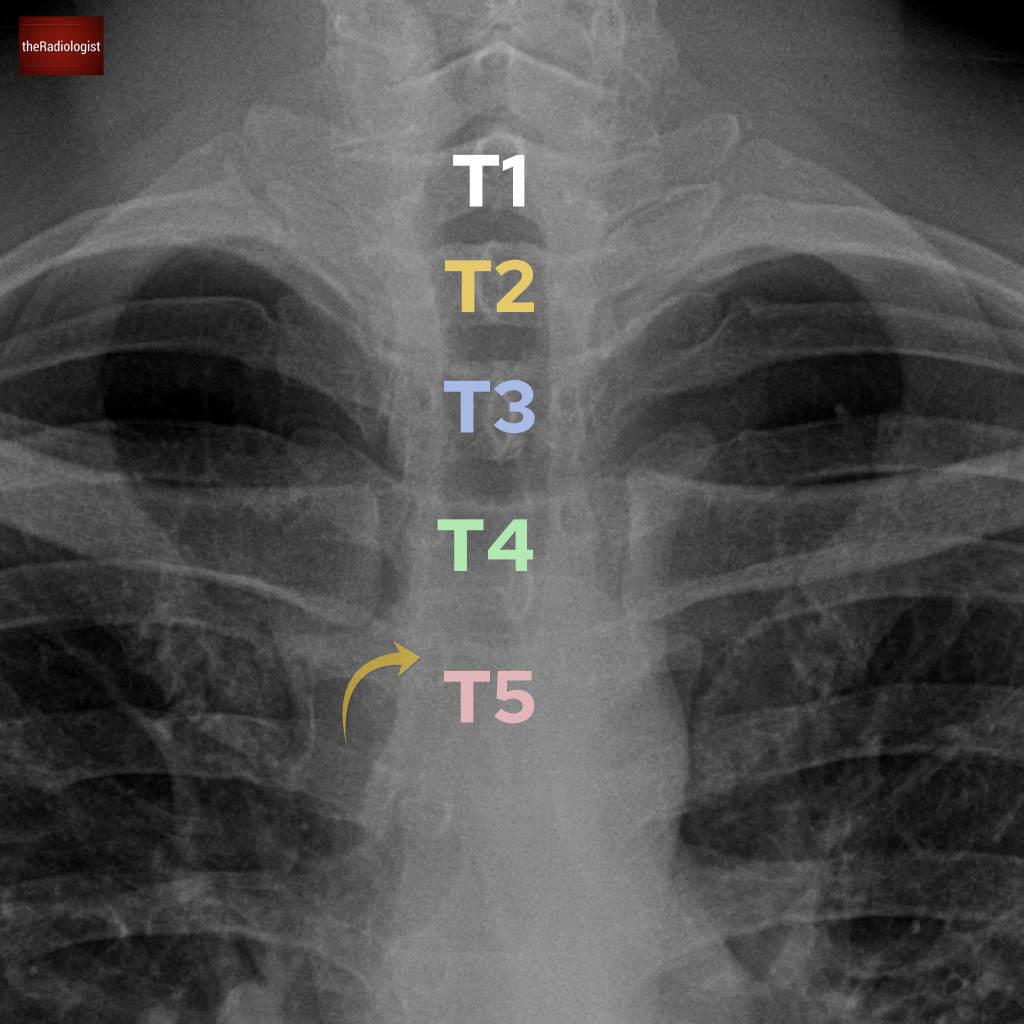

Anatomy Quiz 2

Improve your radiological anatomy knowledge

Ten questions testing your anatomy knowledge!

You will be faced with ten different images from different radiology modalities. Pick the best answer from the five possible answers then submit and scroll down for the explanation.

At the end you’ll receive a final score but don’t worry it is more about picking something up along the way.